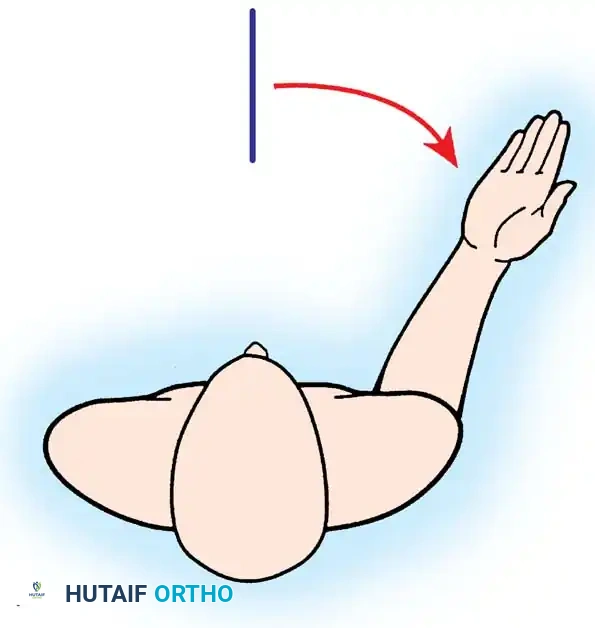

The patient is placed in a modified beach-chair position with the operative arm completely free for manipulation. A standard deltopectoral approach is utilized.

The patient is placed in the lateral decubitus position with the arm draped over a bolster. A universal posterior approach is utilized.